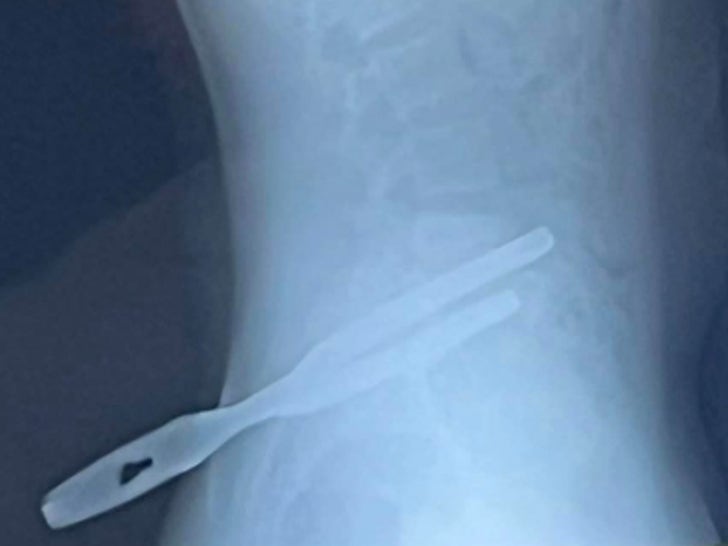

Joey’s mom, Alicia Zeman, shared the graphic pics on Facebook … and as you can see, the tool’s handle is embedded just above his hip while the sheath hangs by the side.

Alicia adds that the pliers were firmly lodged into his bone … the reason why Joey couldn’t pull them out on his own. Joey’s now on crutches after spending a night in the hospital … and will make a full recovery as his internal organs were spared.